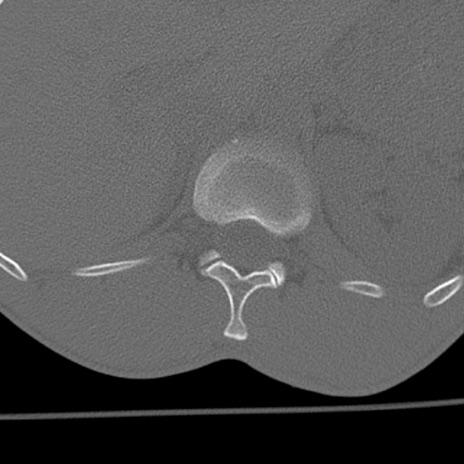

症例3 腰椎CT(横断像)

腰椎CT